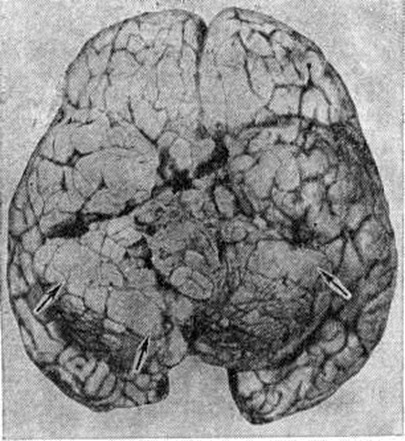

Макроскопически Медуллобластома имеет вид мягкого узла сероватого или серовато-розового цвета, довольно чётко отграниченного от окружающей ткани. Микроскопически опухоль состоит из густо расположенных недифференцированных клеток, образующих иногда своеобразные ритмические структуры в виде правильных или беспорядочных рядов, которые сравнивают с грядами и колоннами (рисунок 1). Особенно характерны микроскопические структуры в виде так называемый розеток, образованных кольцевидно расположенными опухолевыми клетками, отростки которых сходятся в центре розетки. Опухолевые клетки умеренно полиморфны, с многочисленными митозами. Наряду с гиперхромными мелкими округлыми ядрами в клетках Медуллобластома встречаются овальные и вытянуто-овальные, удлинённые, а также более крупные светлые округло-овальные ядра с чётким ядрышком. Строма опухоли скудная, с небольшим количеством преимущественно мелких, тонкостенных сосудов. Очаги некроза и кисты не типичны. Рост опухоли инфильтративный с прорастанием прилежащей ткани и мягкой оболочки мозга, нередко с вторичным врастанием из оболочки в подлежащую ткань. Медуллобластома метастазирует главным образом по ликворным пространствам, в мягкую оболочку и эпендиму желудочков мозга, в которых определяются плоские, сливающиеся между собой белесоватые узелки (рисунок 2), переходящие в диффузные разрастания. Иногда Медуллобластома даёт метастазы в лимф, узлы, кости, органы желудочно-кишечные тракта. |

Рис. 2. | ||